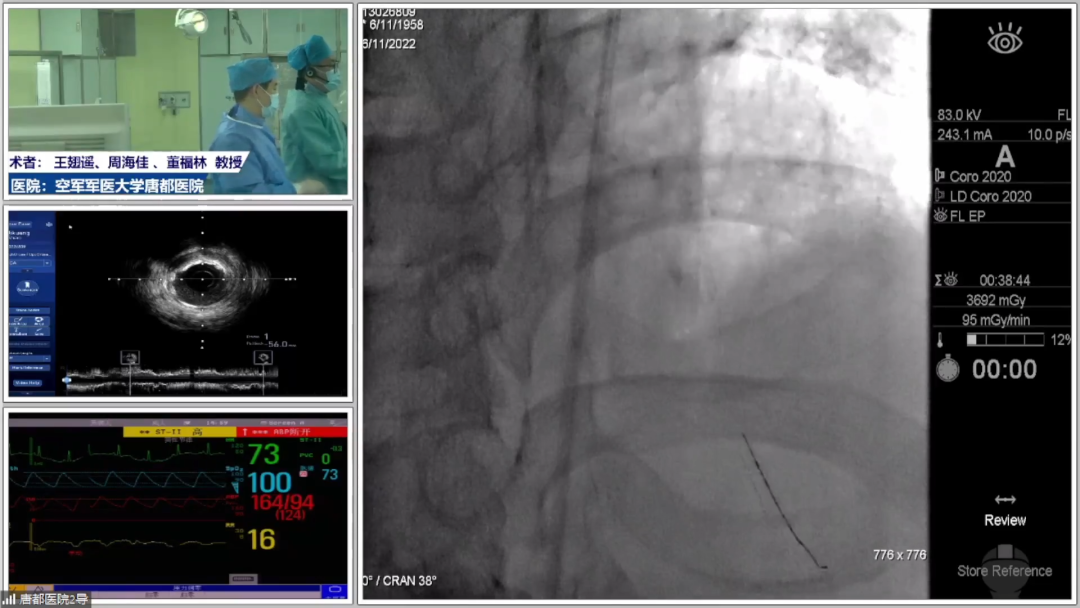

GZ支撑妙用集锦之一:支撑无忧,不惧挑战

学术内容的首个环节特别邀请西安交通大学第一附属医院郭宁教授、浙江大学医学院附属第二医院蒋峻教授、中国人民解放军联勤保障部队第九八〇医院汝磊生教授共同担任主持,同时邀请中南大学湘雅二医院涂涛教授、空军军医大学唐都医院王翅遥教授、陕西省人民医院朱舜明教授共同担任讨论嘉宾,聚焦Guidezilla的强效支撑,李妍教授带来主题讲座,广东省人民医院何文飞教授分享了Guidezilla助力高阻力病变PCI的精彩病例,空军军医大学唐都医院薛玉生教授、马文帅教授展示了使用Guidezilla处理复杂病变的高难度手术演示。

图片

现如今,复杂病变PCI逐渐成为常见临床场景,Guidezilla临床应用也越来越常见。李妍教授认为,Guidezilla应用的核心理念在于提供强效支撑。从设计来讲,相比传统的延长导管,Guidezilla头端柔软,推送力强,操作方便,可以实现快速交换,其优势在于操作灵活、表面平滑,能够为器械输送建立安全通道。手术过程中,使用球囊辅助技术BAT可以有效避免剃须刀效应。

从临床应用场景来看,Guidezilla常用于支撑力不足的RCA病变、高阻力钙化病变、迂曲病变和输送DCB及长支架,从而优化PCI手术效果。此外,Guidezilla II已全面升级,毫无疑问是每位术者必备的利器。

何文飞教授分享了一例Guidezilla助力完成高阻力病变PCI,术前冠脉造影提示LAD近段重度狭窄,中段完全闭塞。术者首先启动正向策略,在微导管支撑下调整导丝进入LAD远端真腔内,由于LAD中段血管较迂曲且有钙化,微导管及小球囊均无法通过LAD中段病变,毫无疑问这是一例器械通过困难的高阻力病变。术者当即决定使用Guidezilla提供强效支撑,顺利将1.2*12mm、2.0*15mm球囊送入LAD中段病变处进行预扩张,并在Guidezilla支撑下顺利植入支架。随后术者再次面临高阻力困境,NC球囊无法到达支架远端,于是术者再次借助Guidezilla的强效支撑顺利将NC球囊送入支架远端进行后扩张,且对支架近中段进行充分后扩张,最终获得了满意的手术效果。

众所周知,器械通过困难是我们处理高阻力病变过程中最常见的障碍,而Guidezilla则是提供强效支撑的神兵利器,常常能助力我们完成介入手术。

随后,李妍教授团队,薛玉生教授、马文帅教授进行了手术演示直播。该患者为老年男性,合并心功能不全,冠脉造影示RCA极度迂曲,近段偏心斑块,中段重度狭窄,钙化负荷重。讨论嘉宾指出,该患者钙化负荷重,需要积极预处理,但同时要考虑旋磨头崁顿风险;此外,IVUS在本病例中具有重要价值,例如评价钙化严重程度,协助支架落脚点选择。术者对此表示了肯定,遂首先行RCA IVUS回撤成像,局部可见360°环形钙化,最狭窄处可见突入管腔的钙化结节。

讨论后术者决定使用直径2.75mm及3.0mm NC球囊预扩张RCA中段重度狭窄处,Guidezilla备用,随后植入3.5*23mm支架并后扩张。此时复查造影却显示支架近段存在局部发白影,经IVUS证实支架近段并无夹层,提示局部发白影可能为血管内膜褶皱所致的手风琴现象,遂结束手术。